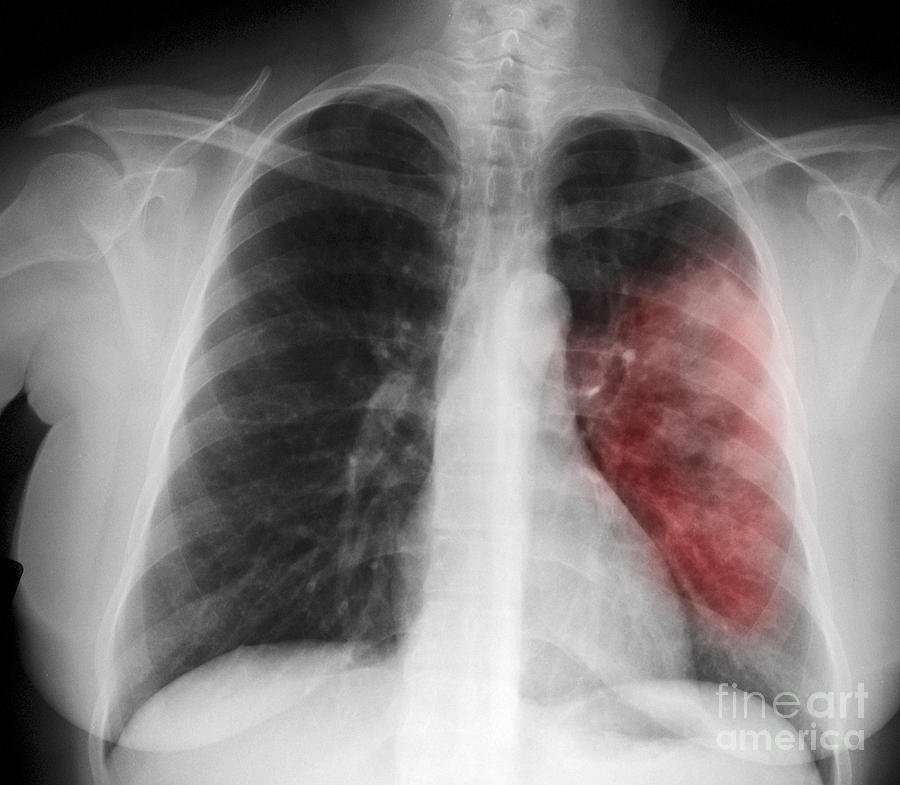

Рентгеновские снимки при пневмоцистной пневмонии